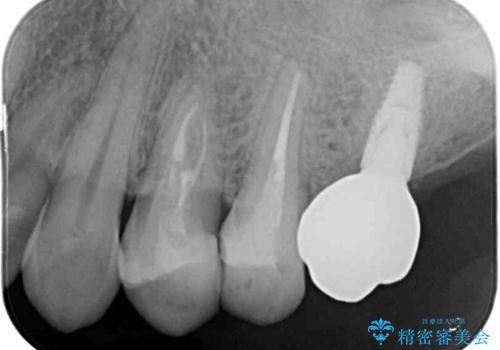

- 以前根管治療を行い、クラウンにする必要があると言われたものの、そのままに放置してしまったとのことで来院された患者様です。

根管治療を行った歯には特に症状がないため、速やかにオールセラミッククラウンにて補綴治療を行うこととしました。